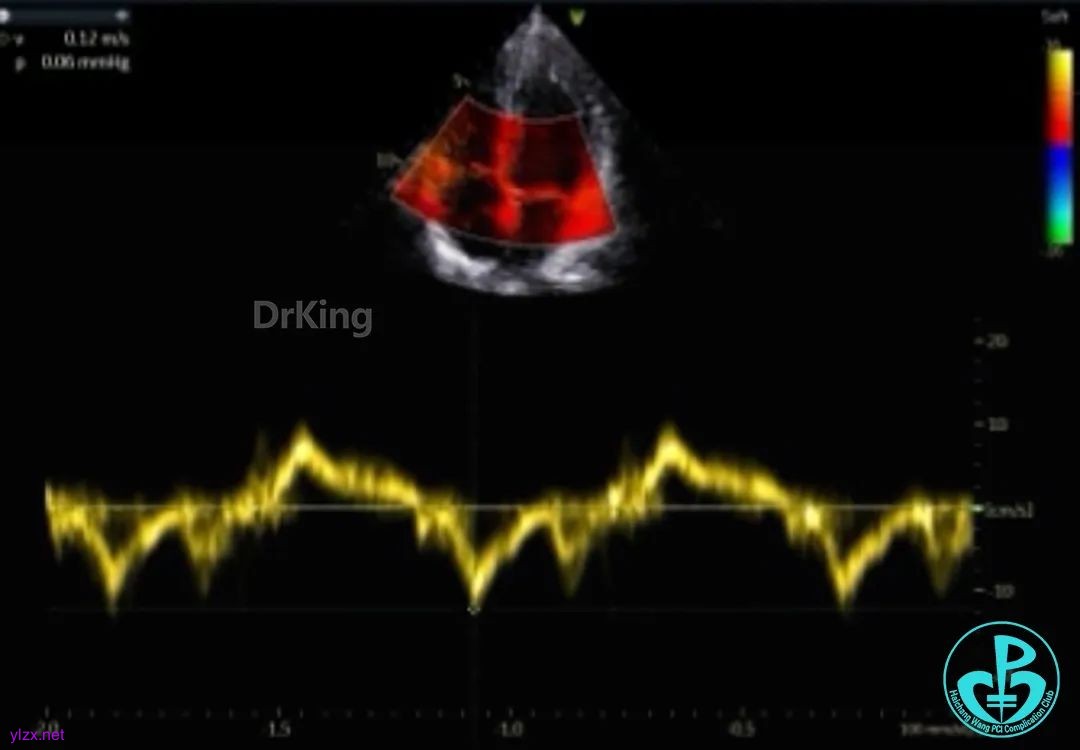

超声检查

房间隔中部有回声中断,测ASD大小:8×8×9mm,CDFI探及左向右分流,距主动脉根部0mm,距二尖瓣环10mm,距房顶14mm,距上腔静脉13mm,距下腔静脉11mm。